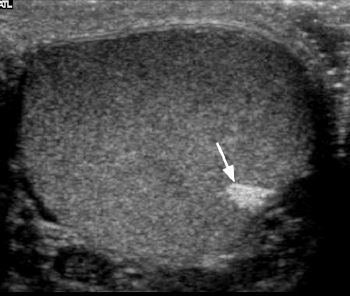

Testicular seminoma

* homogeneous, hypoechoic, hypervascular mass - typical for a seminoma * DDx * seminoma * infarct * contusion * hematoma * focal orchitis * focal atrophy * sarcoid * primary tseticular tumors are the most common malignancy in young adults * most common - germ cell tumors * most common - seminoma